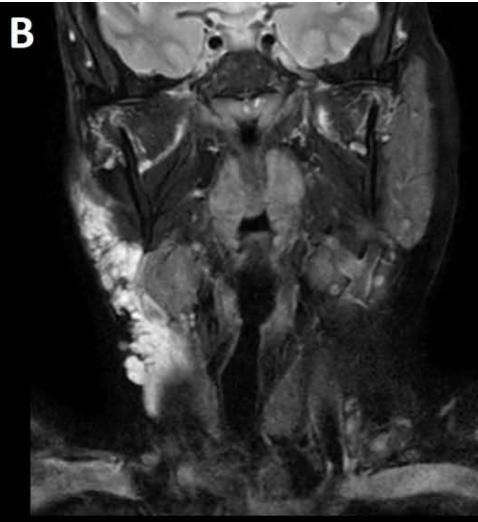

Figure/Patient 2

A case of right mandibular lymphangioma in a 10 year-old boy, hypoechoic with some septations and no blood vessels (A) and hyper-intense on T2 axial (B) and coronal (C) MR scans.